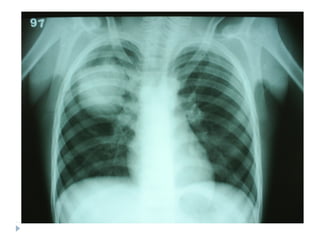

Radiografia

 Não precisa ser feita na criança tratada em casa.

 Radiografias em perfil não precisam ser feitas rotineiramente,

em todos os casos.

 A imagem radiológica não distingue etiologia viral ou

bacteriana.

 Não se recomenda radiografias de controle, exceto para

pneumonias complicadas, como com derrame pleural ou

atelectasia.

Manifestações radiográficas

Pneumonia por Mycoplasma, sorologia positiva